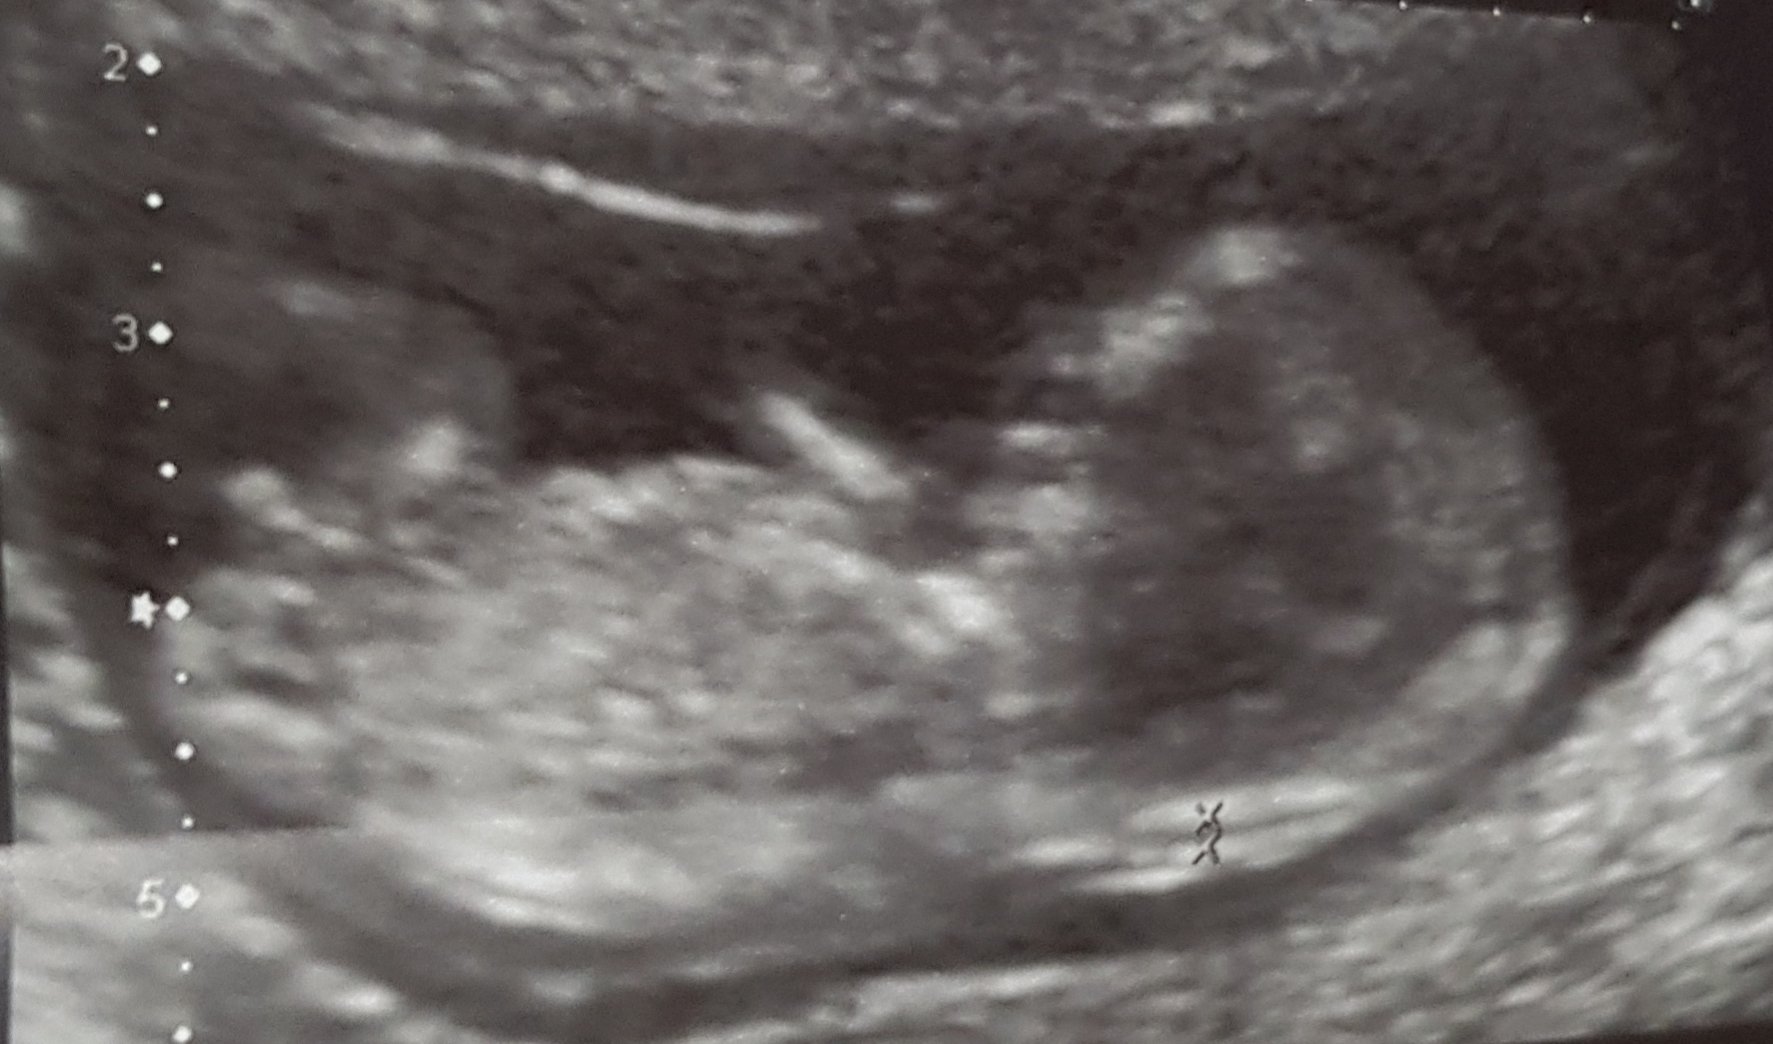

merhaba bu da benim gorūntüm

Resmi yukledim bakabilir misiniz? Burda 13+6 haftalik..tam nub gorunuyormu bilemiyorum bir tanede renkli foto vardi ama o yuklenmiyor malesef🙁